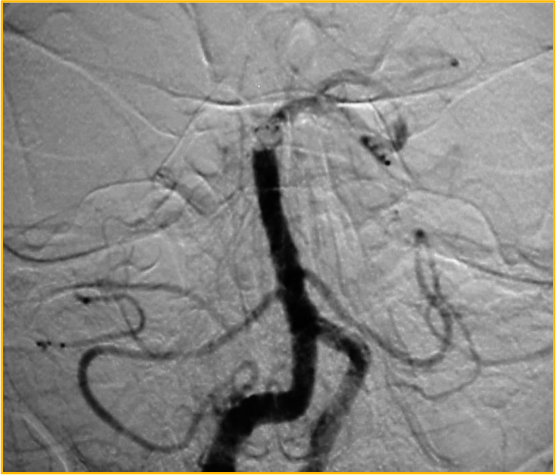

Cerebral angiogram showing basilar artery occlusion

Cerebral angiogram: performed approximately 4.5 hours after symptom onset in a 31-year-old man demonstrates an occlusion of the distal basilar artery.